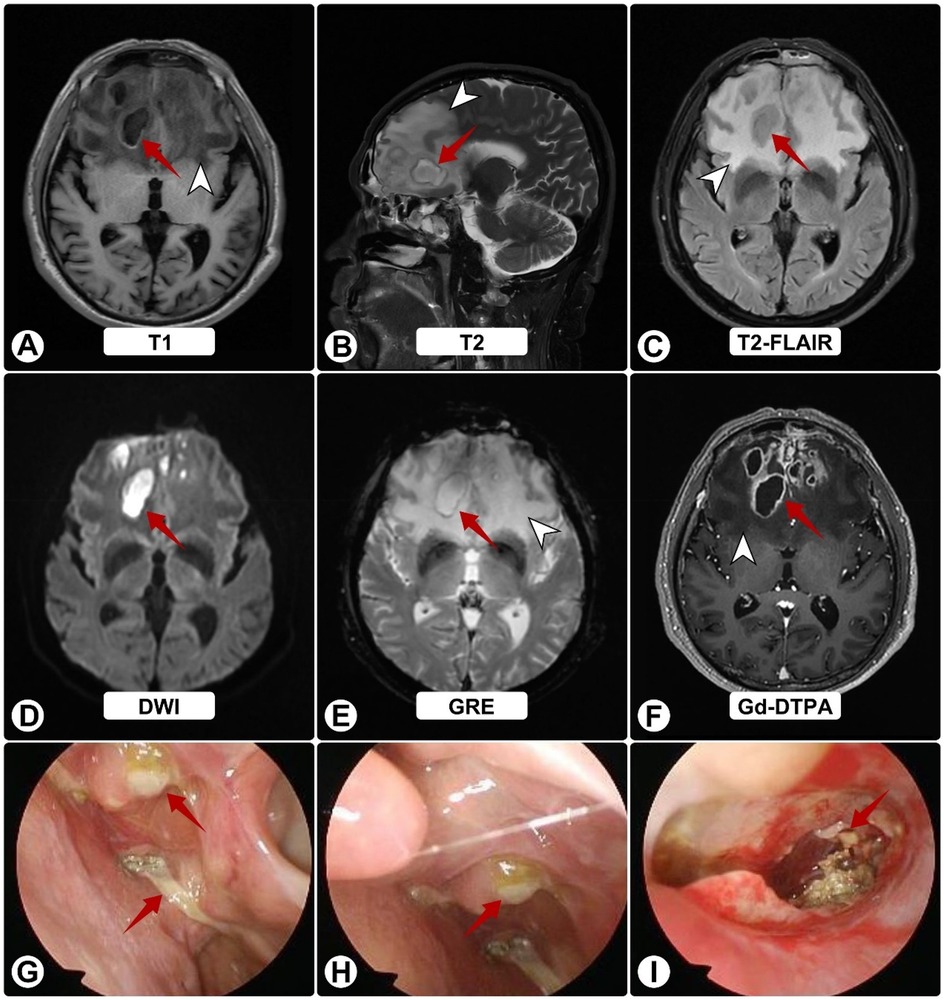

Two months thereafter he presented to our center. MRI demonstrated bilateral frontal lesions with extensive edema and ring enhancement (Figures 1A–F); nasal endoscopy confirmed purulence (Figures 1G–I). Pre-operative CT showed anterior skull-base sclerosis and erosion consistent with osteomyelitis (Figure 3A). Laboratory tests revealed leukocytosis with neutrophilia and mildly elevated CRP; HIV screening was negative. Serum galactomannan (GM) was negative.

Figure 1. Brain MRI and nasal endoscopy on admission. (A–F) White arrowheads indicate surrounding edema; red arrows show abscesses. MRI shows bilateral frontal lesions appearing hyperintense on T1 (A) and T2 (B), and isointense on FLAIR (C) Post-contrast images (D–F) reveal ring enhancement of lesions with extensive vasogenic edema and midline shift. (G–I) Nasal endoscopy shows purulent sinus secretions (red arrows).

MRI and endoscopic images showing various brain scans and nasal passage details. Panels A to F depict brain scans in T1, T2, T2-FLAIR, DWI, GRE, and Gd-DTPA sequences, each marked with red arrows indicating areas of interest and white arrowheads suggesting additional focus areas. Panels G to I show endoscopic views of the nasal passages, highlighting abnormalities or lesions with red arrows.